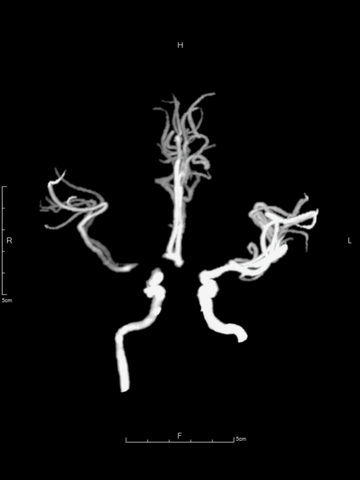

颈内动脉T栓塞大范围严重低灌注的原因

在此患者,由于脑血管发育变异,左侧大脑前动脉A1段未发育,左侧大脑前动脉由右侧大脑前动脉A1经前交通供血,故当右侧颈内动脉T1栓塞时,无法获得前交通代偿,从而导致很大范围的严重低灌注,包括右侧半球和左侧大脑前动脉供血区,也是临床症状严重的原因所在,NIHSS平分达20。

颅脑CTA:右侧颈内动脉分叉部闭塞,累及MCA和ACA近端,颈内动脉分叉部可见血管高密度影。

CTP:右侧半球和左侧大脑前动脉区大范围严重低灌注区,核心梗死主要位于额叶,可见大范围“组织窗”。